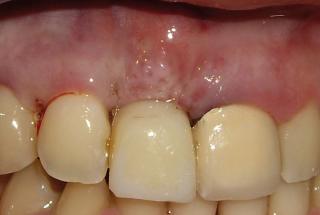

Clinical cases

MPI closely monitors clinical cases in the market to ensure their correct functioning and successful outcome.